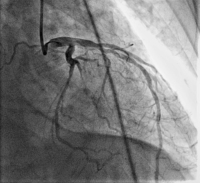

Koronarangiographie

Abbildung 4: CAG-Befund mit LAD und CX-Stenosen

CAG

CX

Kardiologie

LAD

Stenose